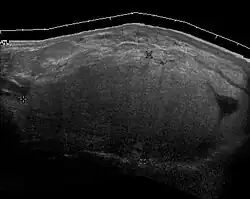

Medical ultrasonography of a lipoma in the thenar eminence: It is hyperechoic compared to adjacent muscle, and relatively well-defined, with miniature hyperechoic lines.[23] -